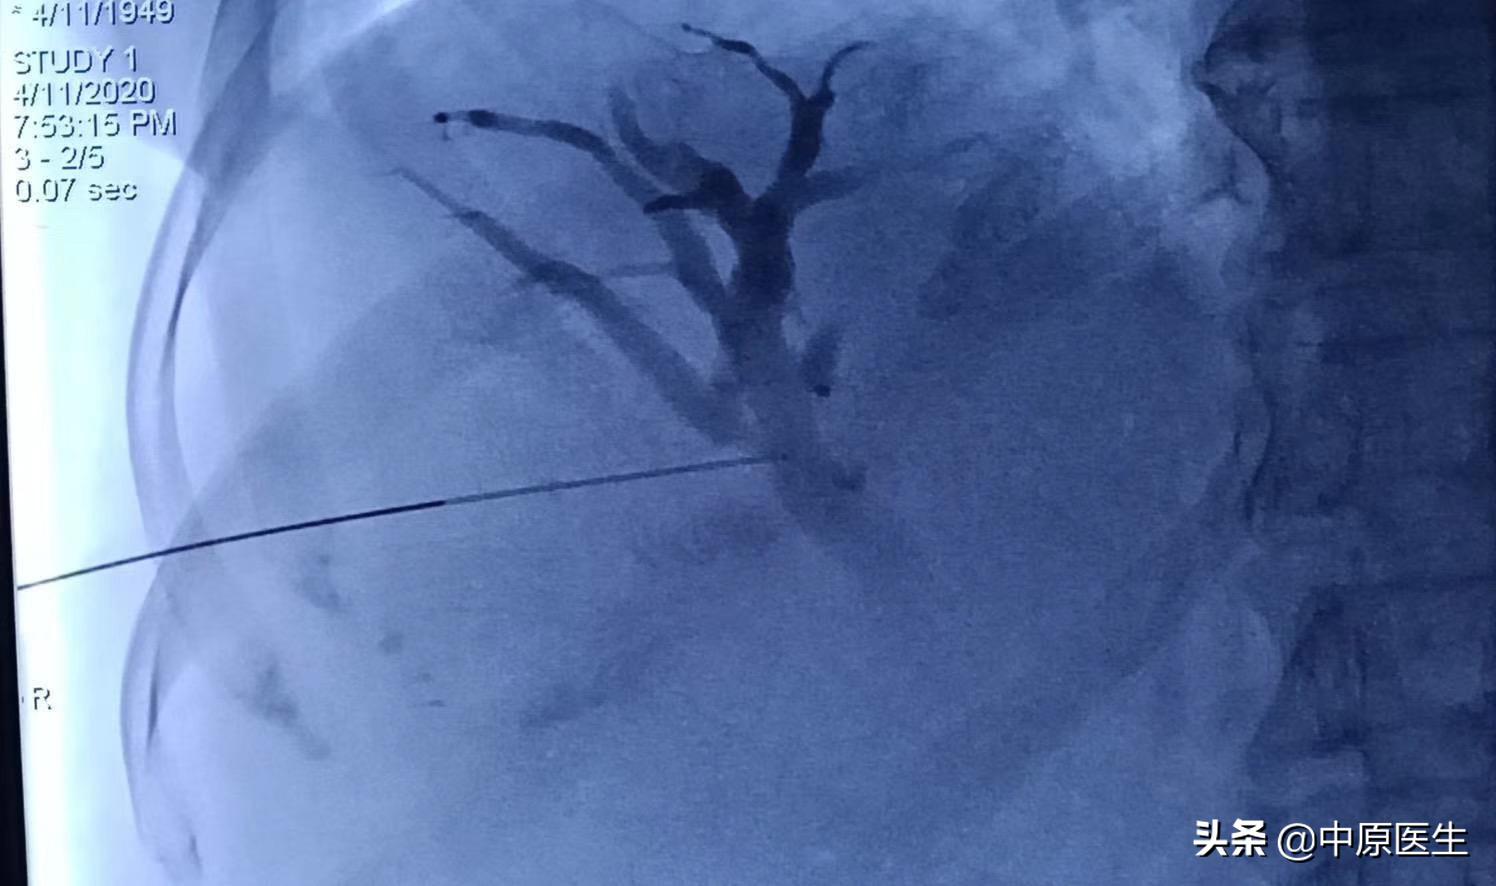

经过消化内科积极准备,病人当天晚上就躺了我们的术台上,那时的患者,正在寒颤,我们迅速消毒,铺巾,准备好手术器械,定位、局麻,从右侧胸壁腋中线第十肋间一针穿刺进入肝右胆管,依次送入扩张鞘,导丝,外引流管,随即就抽出了瘀滞的带味道(感染细菌发出来的味道)的墨绿色、带沉渣的胆汁和肠液约100多毫升。因为患者寒颤,身体情况太差,所以我们放弃了再仔细寻找狭窄肠管部位的手术(这时候保命要紧,那个手术可以择期再次进行),冲洗引流管后,固定、包扎。把患者安全转入介入科病房。回到病房十多分钟后,患者的腹胀、寒颤都有了明显减轻。精神状态也好了很多。看着自家老人转危为安,这一家子说了数不清感激的话!

我们做这个经皮穿刺胆管造影+引流管置入术(PTCD)是怎么一回事呢?它是在影像设备引导下,用一根21G(0.80mm)的细穿刺针经皮经肝穿刺胆管,并置入引流管,使胆汁流向体外或十二指肠的一系列技术。主要用于胆道梗阻和急性炎症的治疗。PTCD不受胆管手术影响(如胆肠吻合术等),对患者的身体要求相对较低,创伤小,缺点是对原发病的治疗有时候会力不从心。